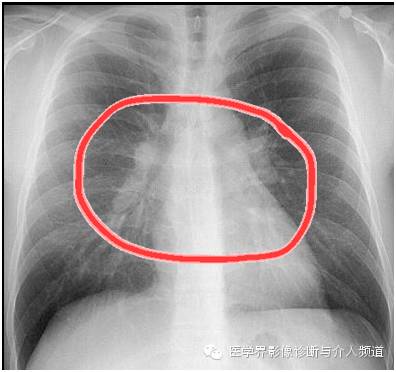

异常:双肺门淋巴结肿大。

到这里一张胸片中观察到的异常就结束了,再结合非常重要的临床病史,你得想到这个病–结节病,本病例为急性结节病。